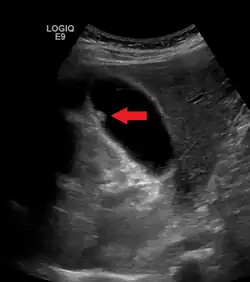

Die Diagnose wird in der Sonografie gestellt. Hier zeigen sich Polypen als Erhebungen der Gallenblasenwand, die in das Lumen, also nach innen, hineinragen. Pseudopolypen zeigen ein typisches Artefakt, das als „Kometenschweif“ bezeichnet wird. Dieses fehlt allerdings häufig, sodass echte und Pseudopolypen im Ultraschall nicht sicher zu unterscheiden sind.[4]